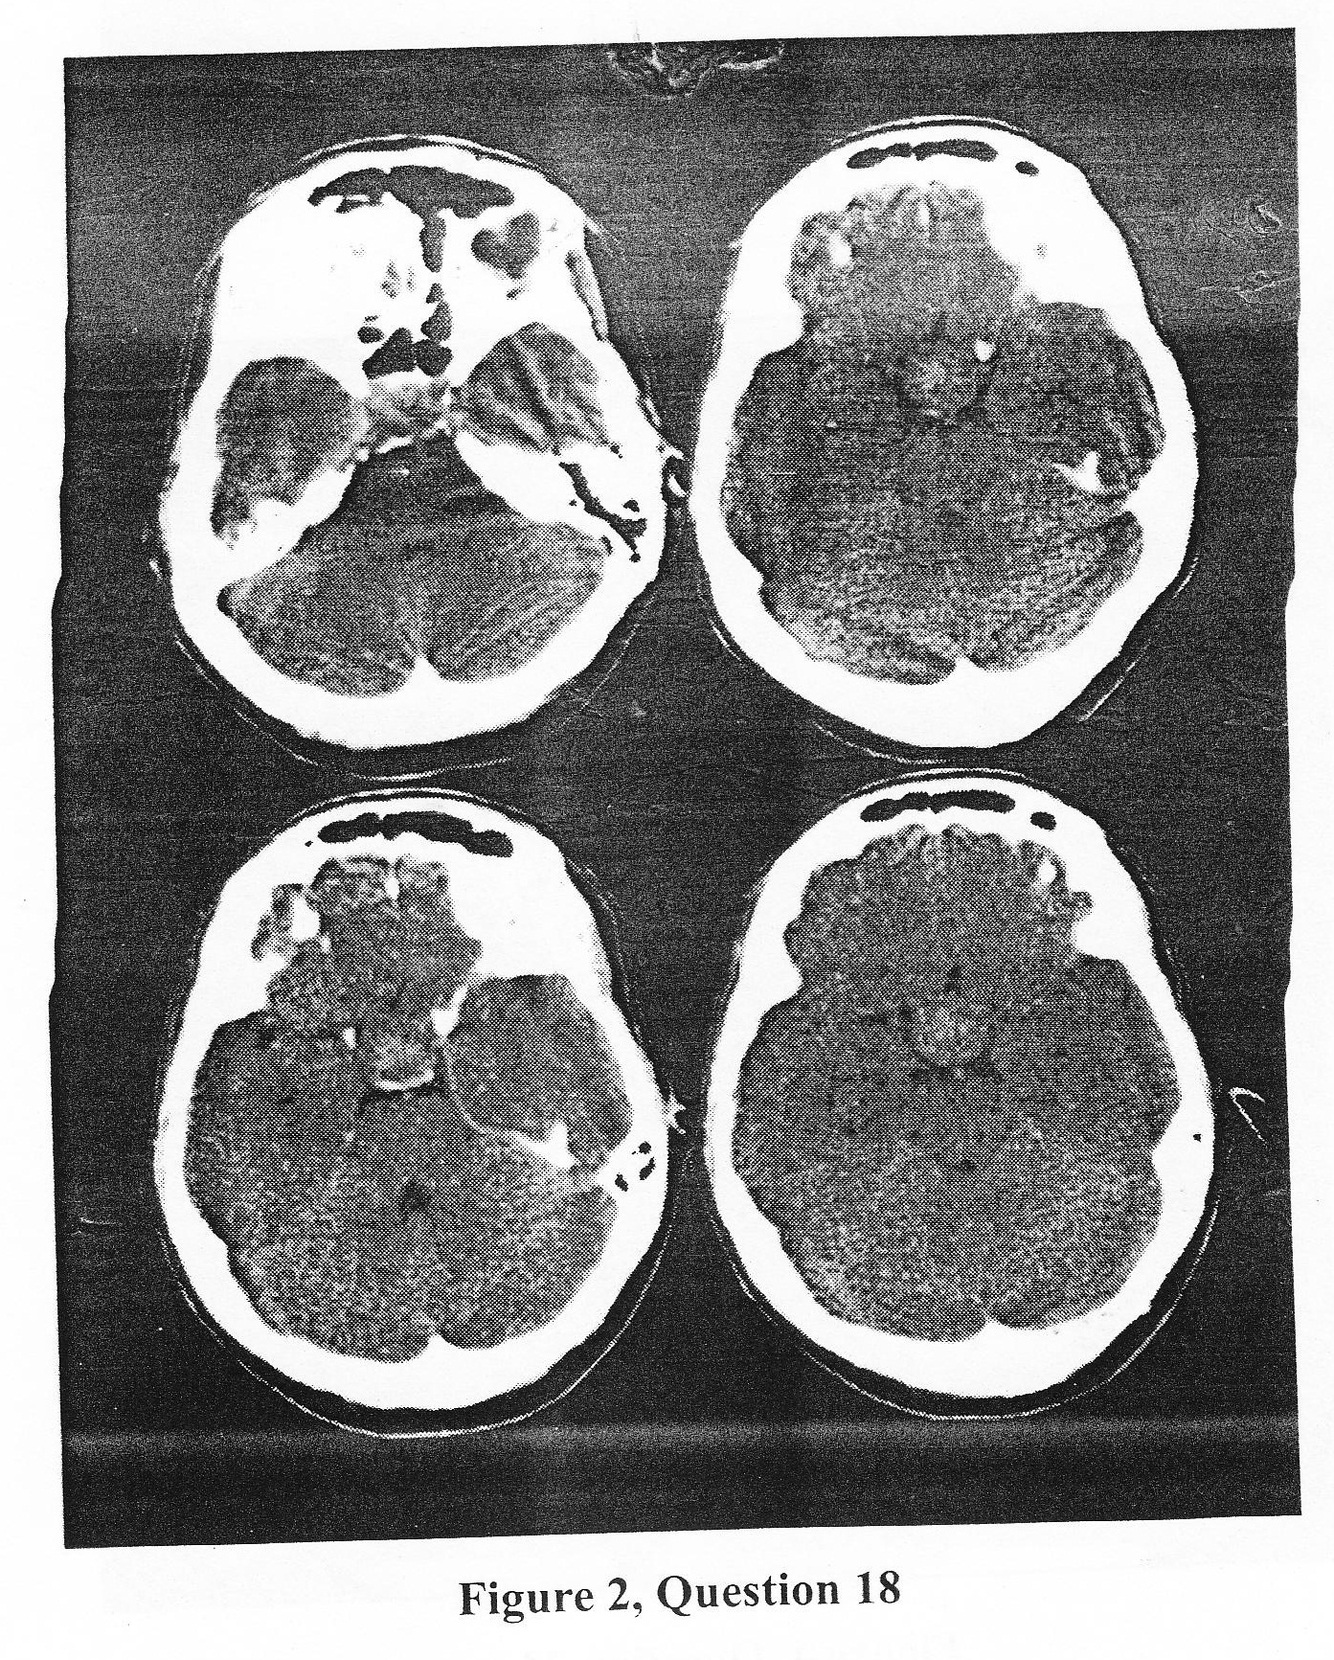

A previously healthy 56-year-old male arrives at the emergency room with a three day history of sudden onset global headache and nausea with several episodes of emesis that have diminished in intensity over the ensuing three day but remained, and progressively severe fatique of one-day duration with recent abdominal pain. The patient’s exam is unremarkable with no evidence of acute peritoneal signs and mimimal meningeal nuchal rigidity. A CT head scan was obtained (Figure 2) and you are consulted. After review of the head scan your next response should be :

a. Lumbar puncture for Cerebrospinal fluid levels

b. Cerebral engiogram

c. administer parenteral glucocorticoids

d. Order an delectroencephalogram (EEG)